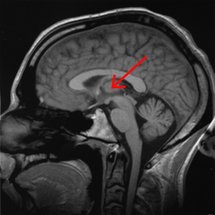

La flecha señala la ubicación del tálamo en el cerebro. Fuente: Wikimedia Commons.

Los científicos han conseguido averiguar que una estructura conocida como tálamo se encarga de filtrar la información que percibimos para que finalmente la corteza cerebral genere las imágenes.

Sin embargo, la corteza tiene "un diálogo muy intenso" con otra zona del centro del encéfalo, el tálamo. Pues bien, "nosotros estamos estudiando esa comunicación que se establece entre el tálamo y la corteza", apunta Mariño, "aunque la imagen se forma supuestamente en la corteza, el tálamo es un filtro fundamental de la información y esa filtración depende del contexto".